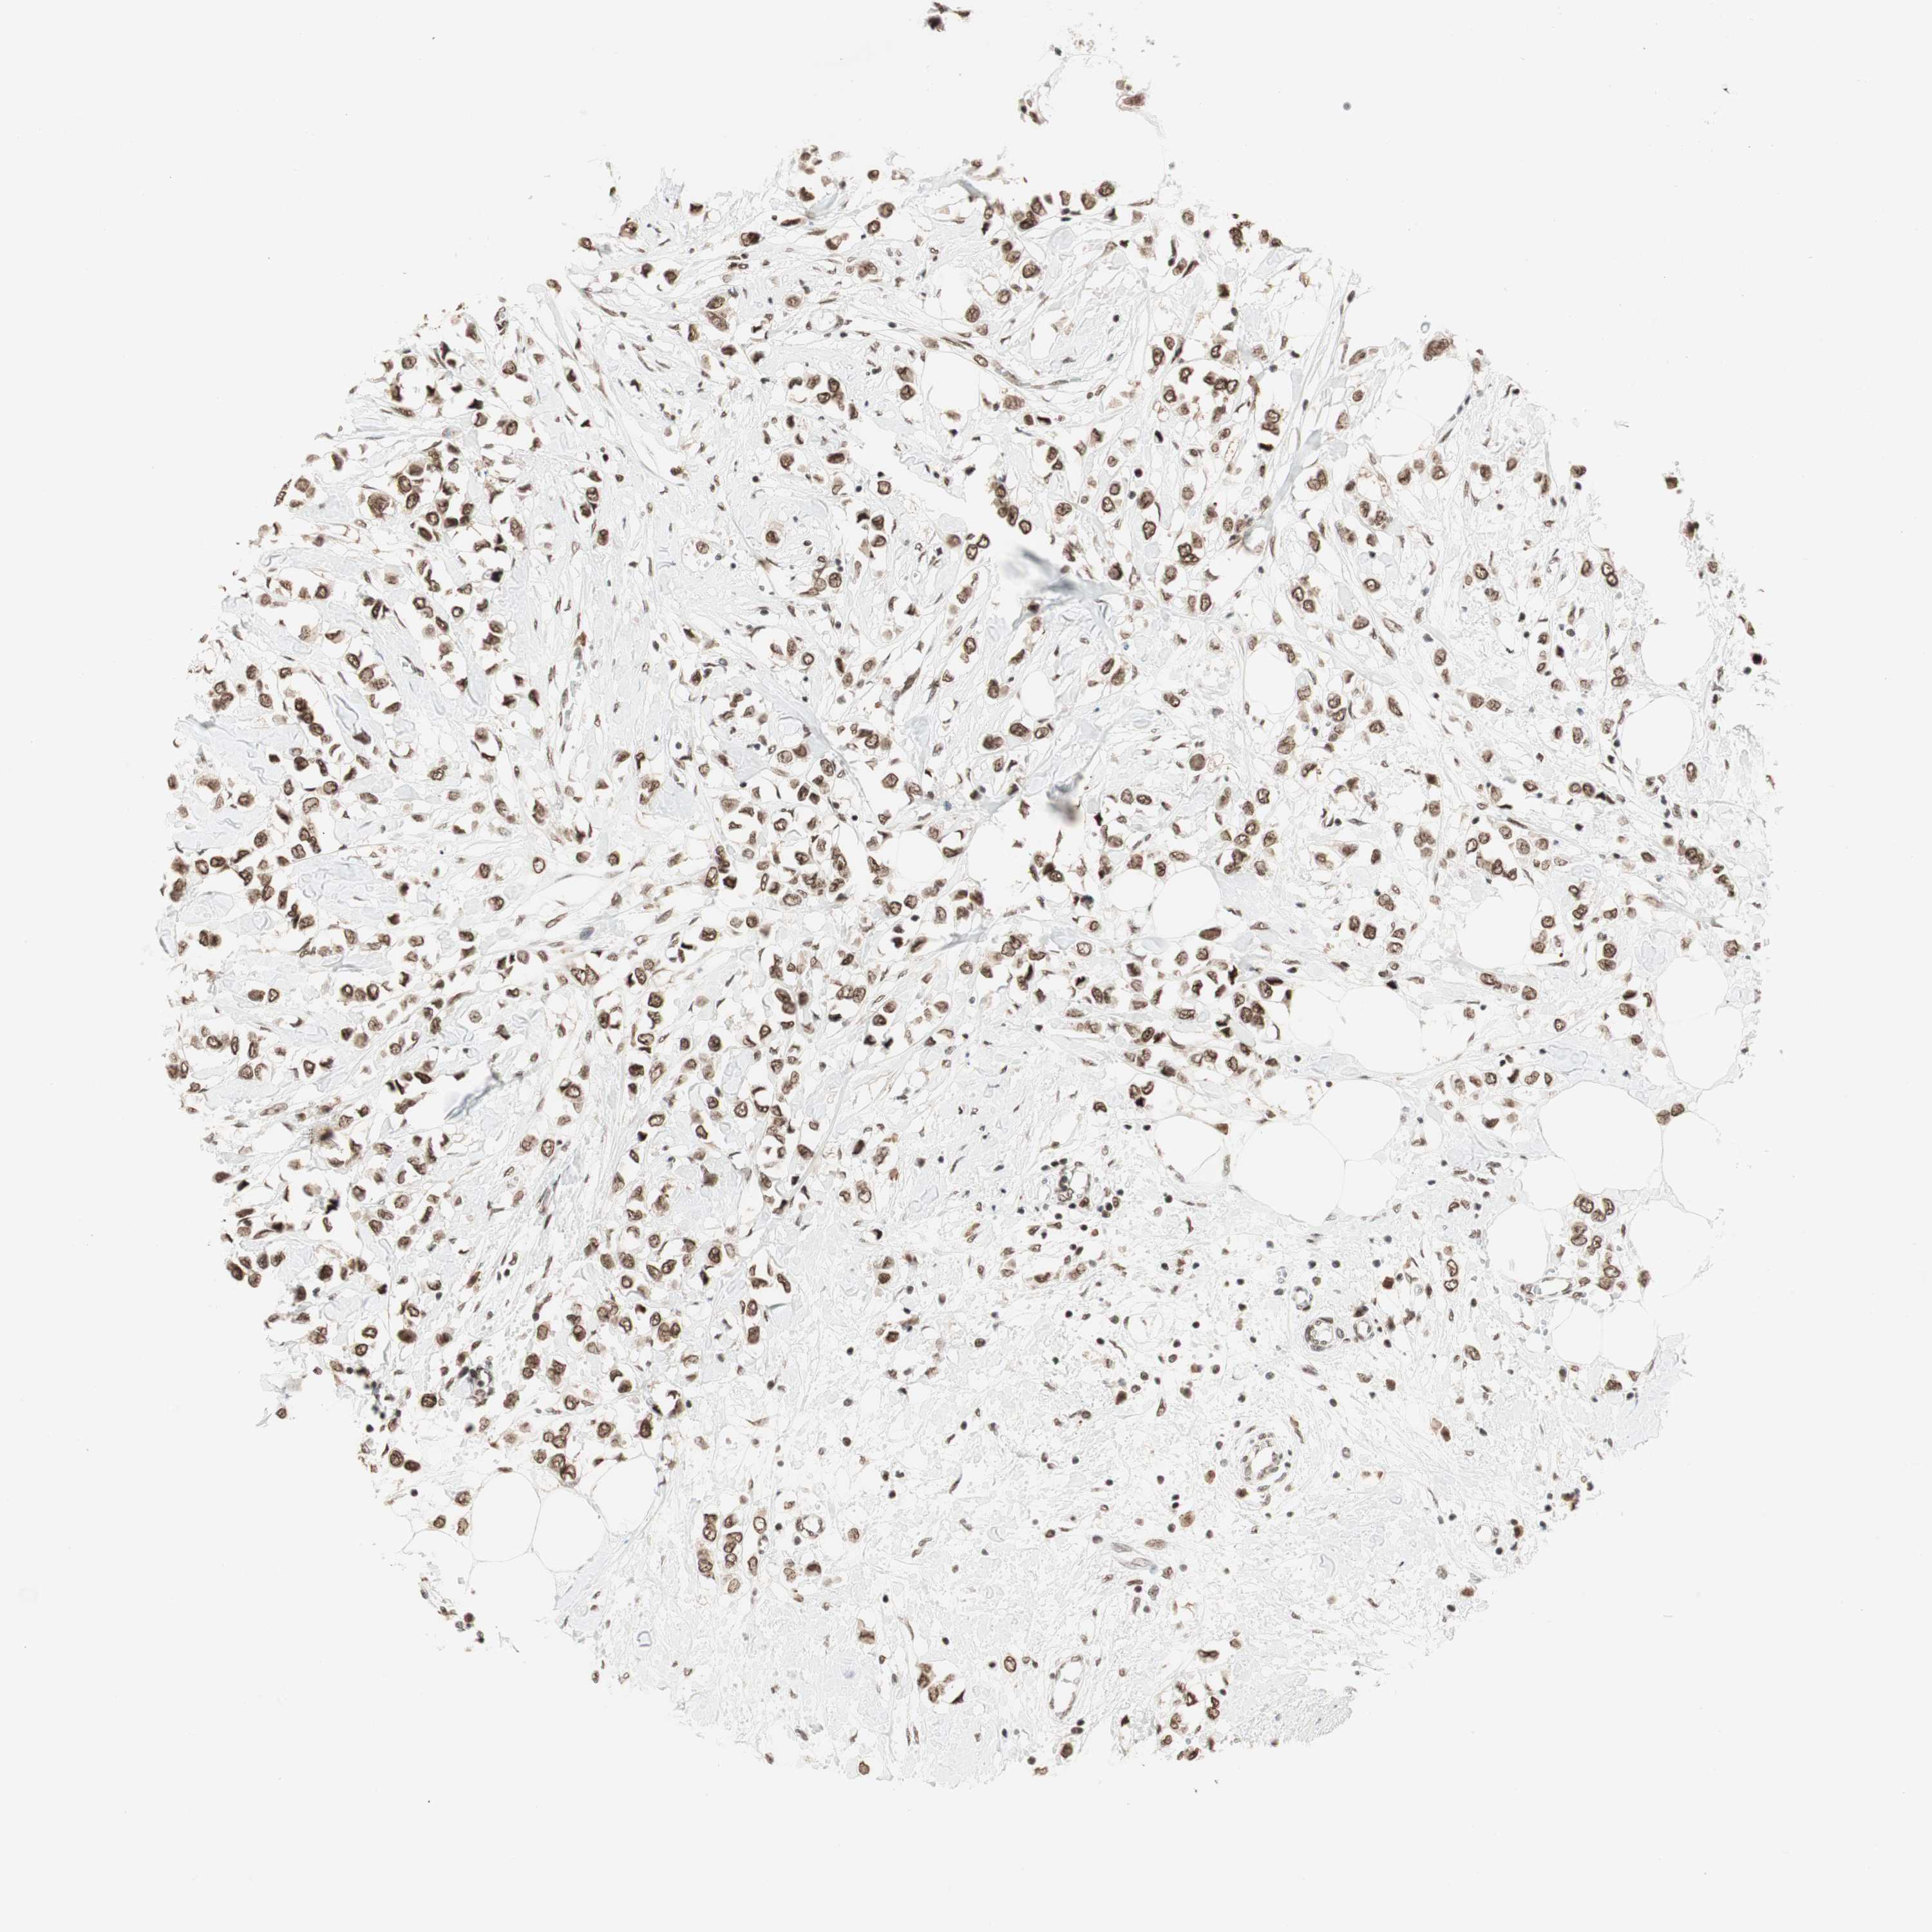

CANCER BREAST CANCER Show tissue menu

BRCA TCGA BRCA VALIDATION PROTEIN EXPRESSION

SMARCE1 is not prognostic in Breast Invasive Carcinoma (TCGA)